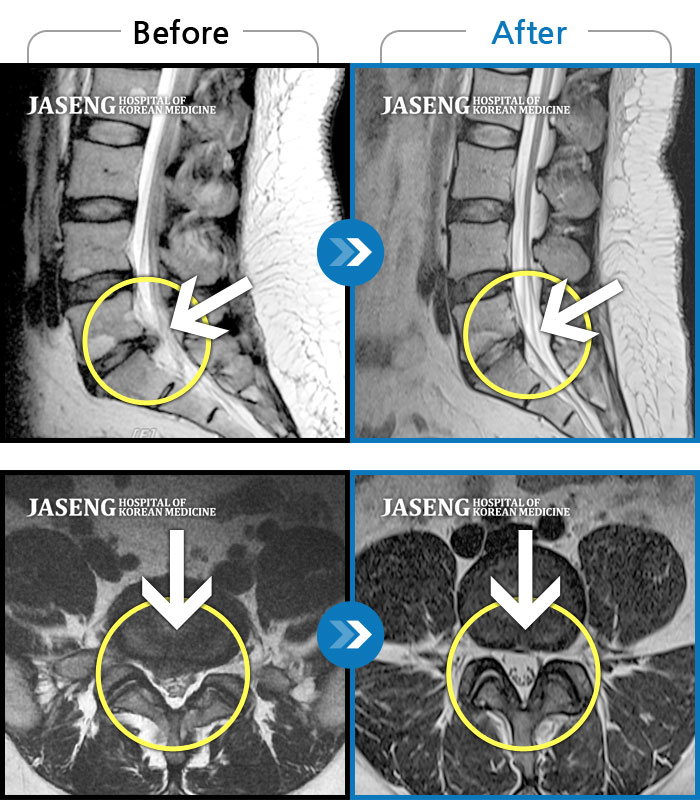

MRI 치료사례

허리 골반으로 움직일때 통증이 있고 다리 저림